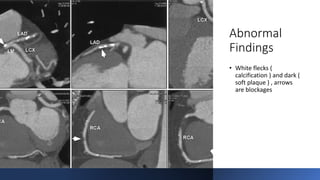

Abnormal

Findings

• White flecks (

calcification ) and dark (

soft plaque ) , arrows

are blockages

Abnormal Findings • White flecks( calcification ) and dark ( soft plaque ) , arrows are blockages